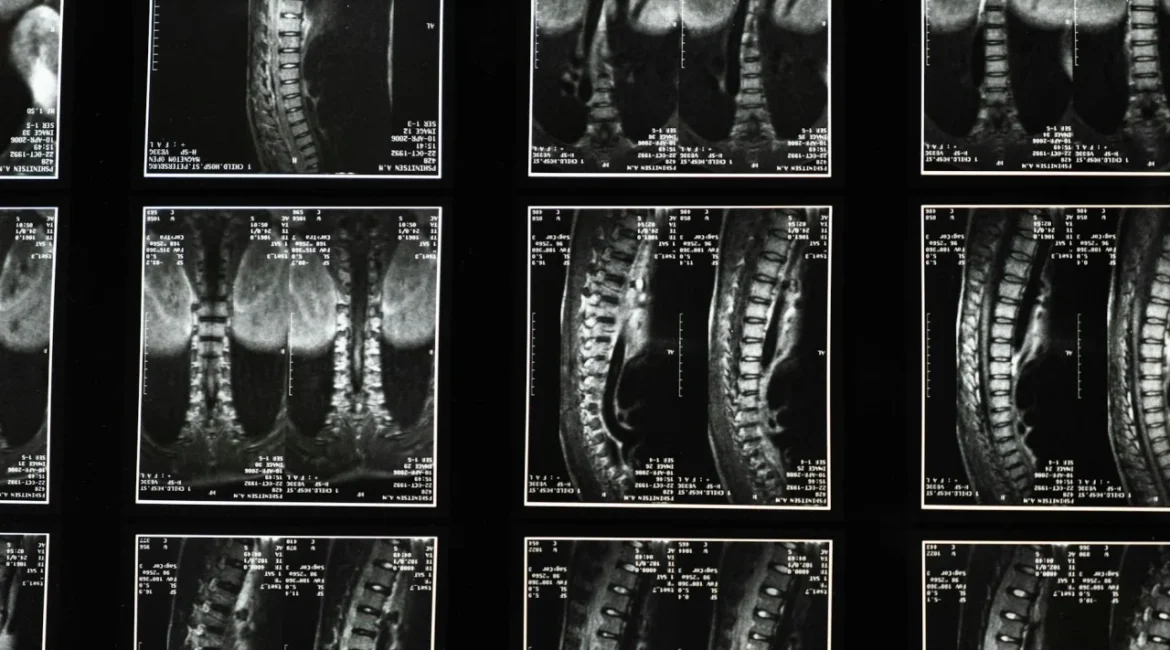

A avaliação inclui exame neurológico, imagem por ressonância magnética e exames laboratoriais. Pacientes devem ter capacidade de consentir ou representante legal autorizado. Informações sobre o uso e segurança da polilaminina são detalhadas na triagem e no consentimento, incluindo aspectos relacionados a Polilaminina Lesão Medular: Onde comprar e como participar do estudo da UFRJ?